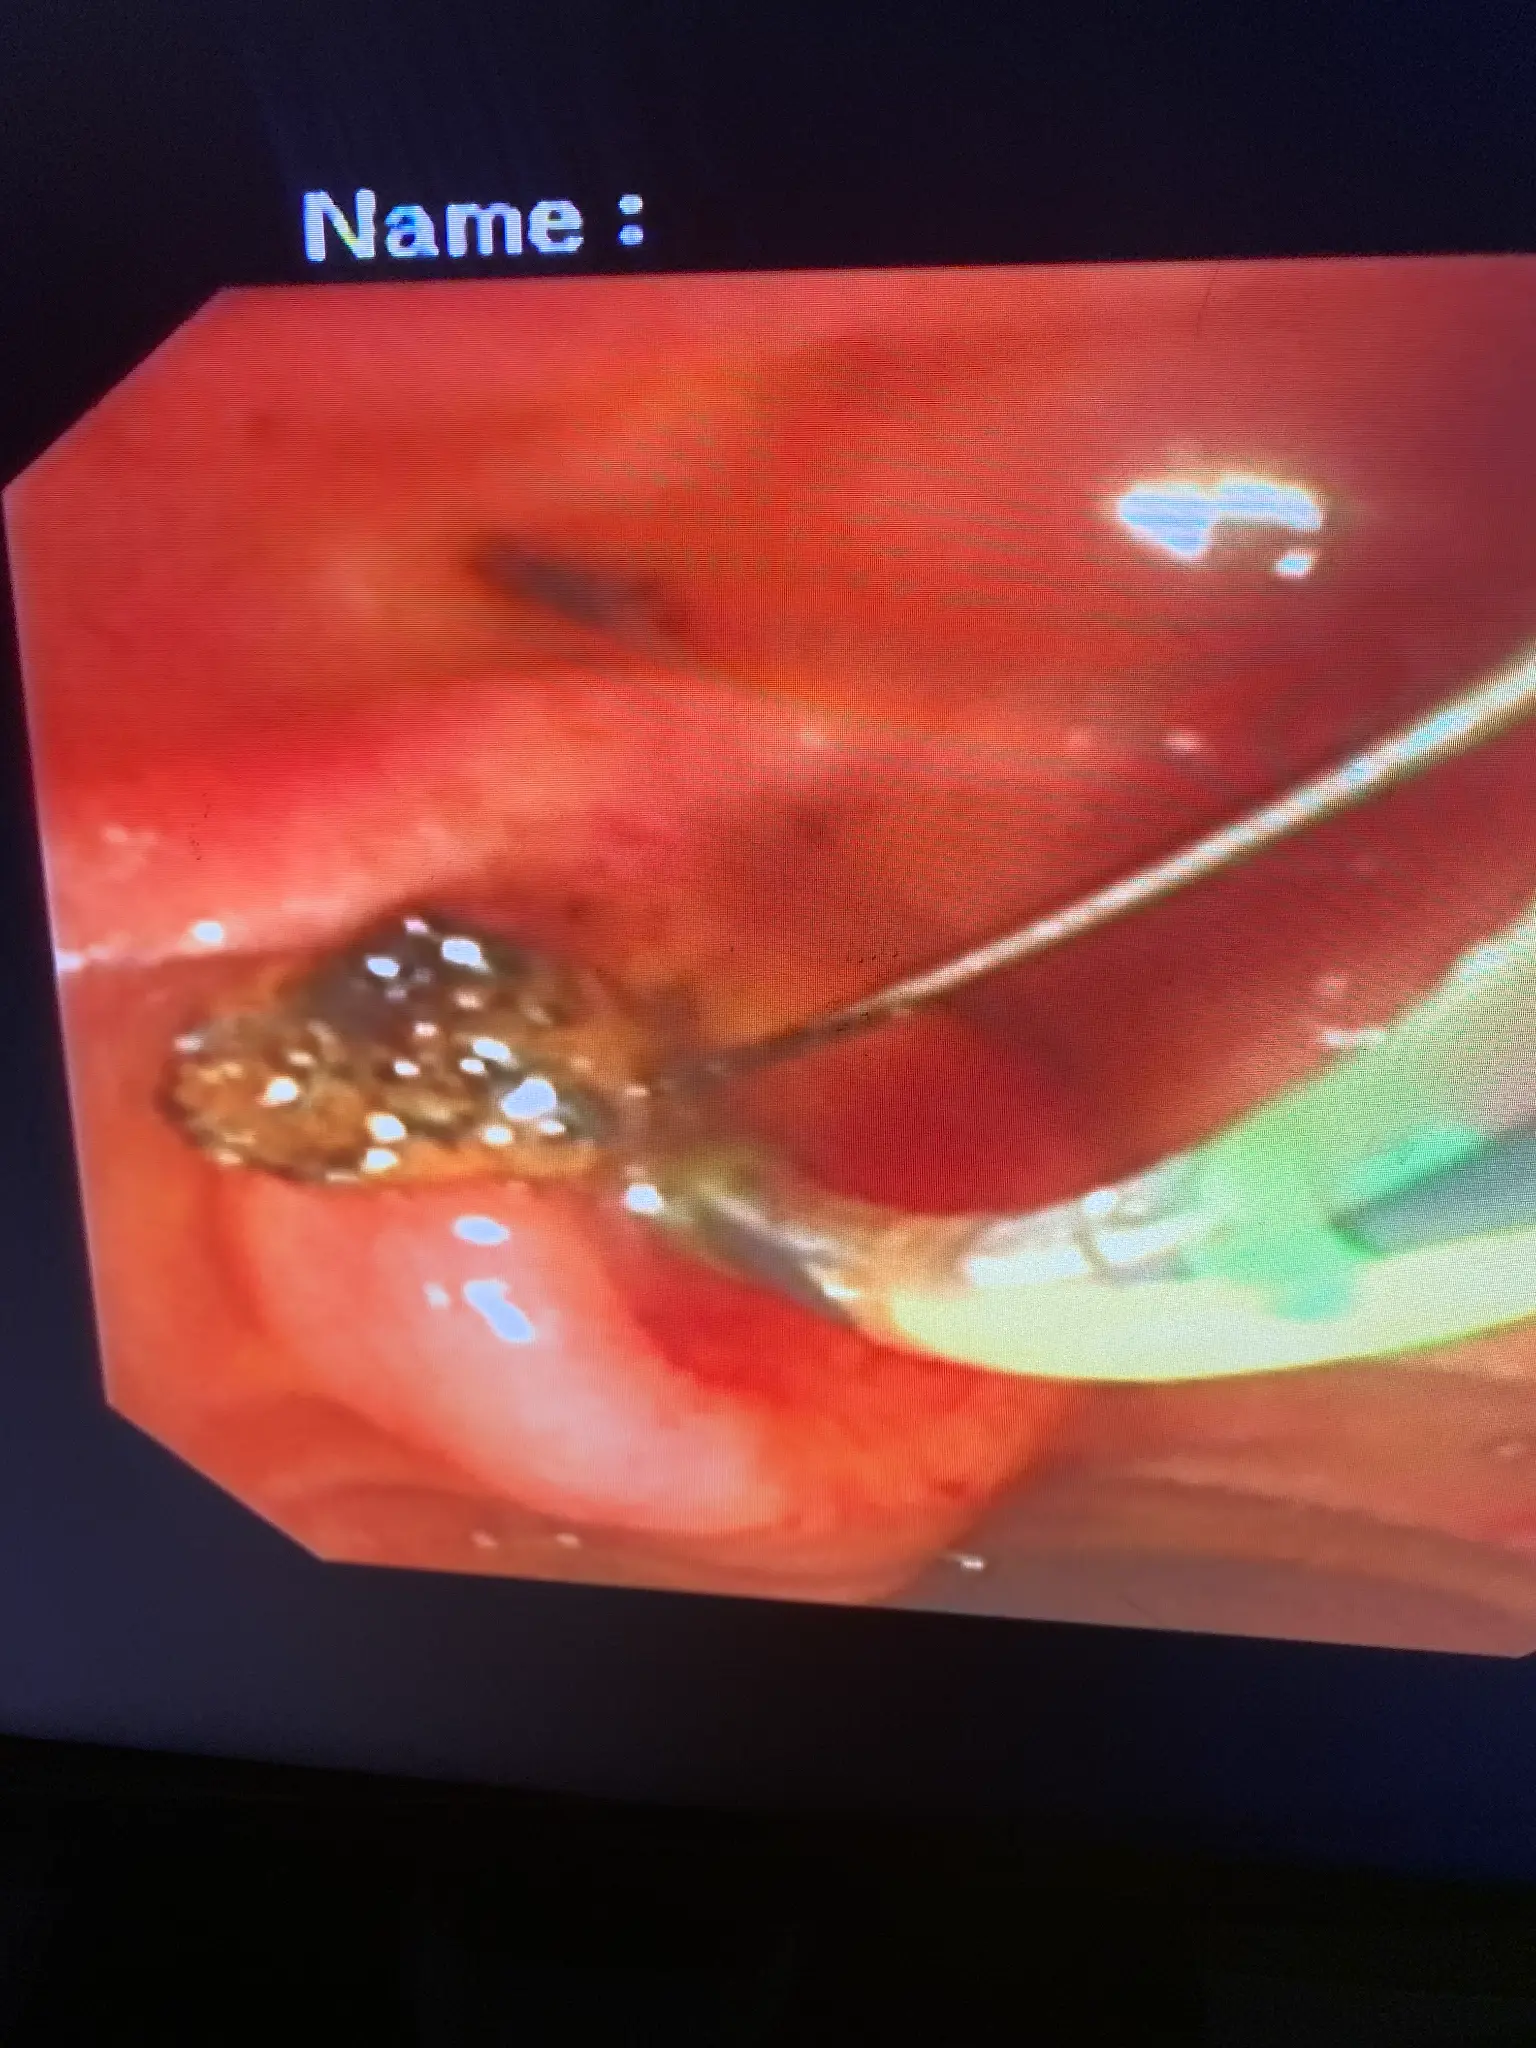

ERCP Intervention Photos

Removal of bile duct stones using specialized baskets or balloons. Larger stones may be fragmented using mechanical lithotripsy or laser techniques before extraction.